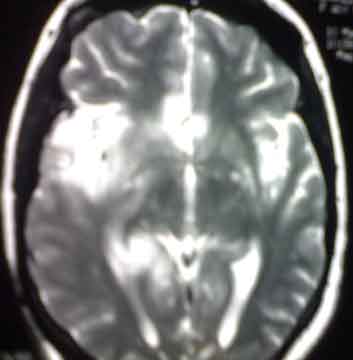

MRI for a female patient aged 41 who presented in a state of disturbed

conscious level which preceded days before by fever, headache,

hallucinations, behavior changes and weakness of lower limbs.

What is the diagnosis?

It is a case of "Herpes Encephalitis". Note

the obvious temporal lobe involvement.